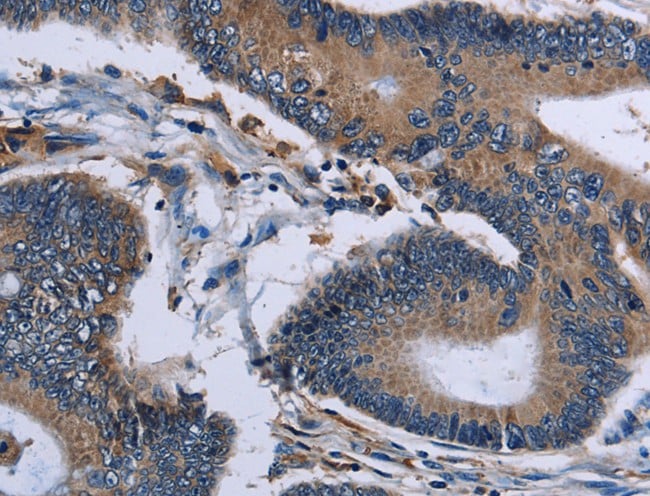

IHC (Immunohistochemistry)

(Detection of human Importin 4 by immunohistochemistry. Sample: FFPE section of human ovarian carcinoma. Antibody: Affinity purified rabbit anti-Importin 4 (Cat. No. AAA211980) used at a dilution of 1:5,000 (0.2ug/ml) Detection: DAB)